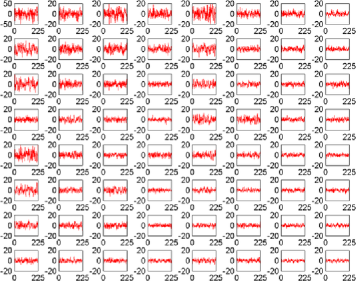

The subject in Figure 3 seems to exhibit strong deviations from stationarity—in fact, the -value associated with this subject is below based on the bootstrap test given in Section 7. It should be stressed that the change detection is a global hypothesis test combined over all components considered. In this way, while taking more components will help increase the chance that the change is present in one, it will come at the cost of the size of the change needed in finite samples for an omnibus test of this type. However, the subject shown in the figure did cause a rejection of the null hypothesis of no change both in the 64 and 125 subspace size omnibus tests. While the pictures in Figure 3 indicate that an epidemic change is indeed a good first approximation for the nonstationarities occurring for this particular subject, more deviation (maybe more change-points) does seem to be present. In Figure 4, a second subject is shown with a much smaller deviation from stationarity (most of the components seem to have little to no possible mean change present), which is significant but does not survive the false discovery rate (FDR) correction (see Section 4.3).

Figures 5–7 show three component time series selected for their different properties. The component in Figure 5 can be seen to be a candidate series for a change to have occurred with the resulting change corrected series visually appearing much more stationary (although it is likely there are other nonstationarities present as well). This series, from subject 01018 in the connectome data set, was found to have evidence of nonstationarities when the sample version of the statistic (given in Section 6.2) was tested on both a 64 and 125 component projection.

When testing subject 48501 from the connectome data, from whom the components can be seen in Figure 4, an epidemic change seems to be quite a good model for several components, but only a small part of the time series deviates from stationarity. For example, component 7 in Figure 6 shows a less pronounced but still plausible epidemic change compared with component 23 of subject 01018 in Figure 5. However, as can be seen in another component (Figure 7) from subject 48501, some of the components seem to be stationary without any change present.

Given that nearly 200 subjects were tested, a multiple comparison correction was implemented using the independent FDR method by Benjamini and Hochberg (1995). The use of an independent FDR is based on the fact that the comparisons are being taken across subjects who can be assumed to be independent of each other. Subject 01018 (Figure 3) survived the FDR correction and evidence was still found of nonstationarities being present. Subject 48501, whose projections are seen in Figure 4, also rejected the null hypothesis but only at about a 3% level, hence not surviving the FDR correction.

Finally, in Figure 2 the subject shown has components which do not indicate level shifts and, in fact, the null hypothesis is not rejected for this subject, either with or without FDR correction.